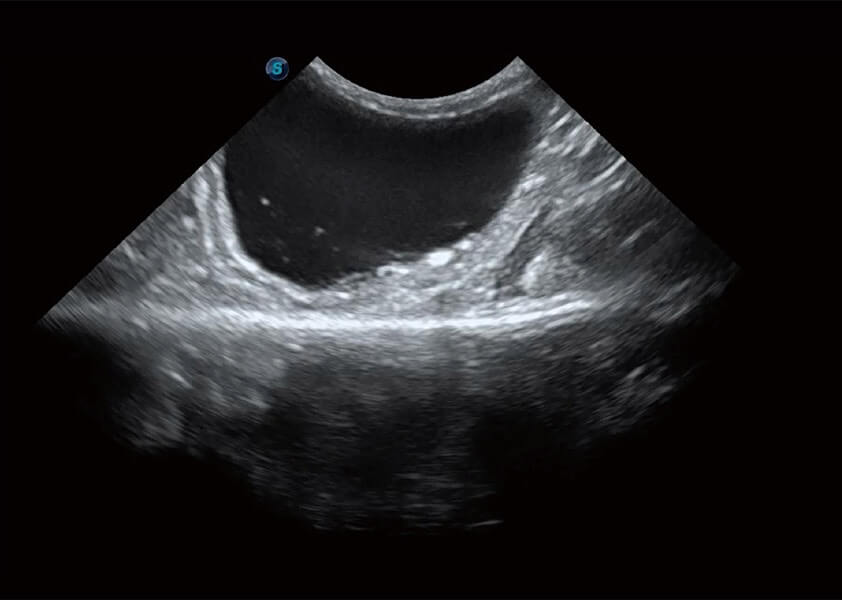

ProPet 60 作为一款高端台式动物超声设备,为动物医生的日常诊断提供了一系列贴合动物临床需求、解决临床实际问题的高级成像功能。凭借全系列高清探头,满足医生对腹部、心脏、生殖、浅表、肌骨等成像的所有需求,切实帮助您提升检查效率,提高诊断信心。

动物是人类最亲密的朋友和最值得信赖的伙伴。新葡的京集团8814检测站也一直致力于探索动物专用的超声影像解决方案。 全新推出的ProPet系列,是新葡的京集团8814检测站在动物超声影像智能化、专业化、精准化的一次跨越式革新。动物不能用言语来表述自己的不适,通过超声影像,ProPet系列搭建了动物医生与不同物种沟通的“桥梁”,为动物医生注入了“治愈之力”。